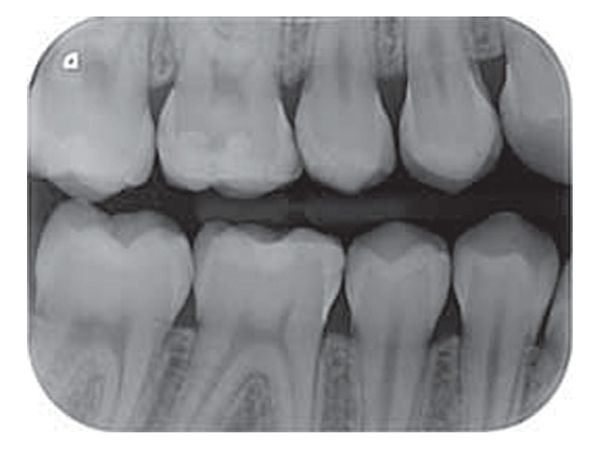

Chất lượng hình ảnh rõ nét

Nhờ công nghệ PCS, VistaScan Mini có thể giúp giải quyết các vấn đề về sâu răng D1, các tổn thương về nội nha xuống đến ISO 06. Với độ phân giải hình ảnh 22 lp/mm, 16-bit (65.536) thang xám.